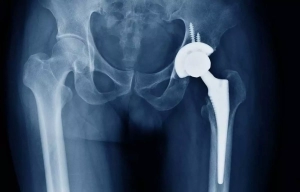

Larger femoral heads in Hip Implants Lower Revision Risk in hip Arthroplasty

A new study published in the The Journal of Arthroplasty found…